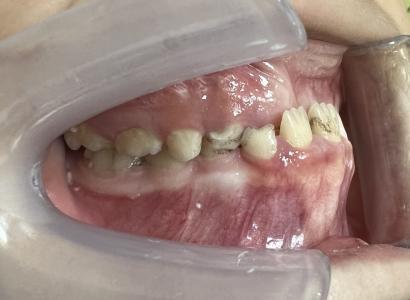

案例一:

治疗前